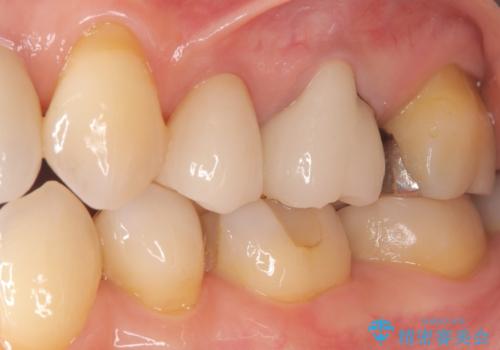

最終的な被せ物には、周囲の歯と自然になじむような色合い・透明感を持つセラミックを採用。形も元の歯に近づけ、違和感のない見た目と噛み心地を再現しました。

治療後には「見た目がきれいになって自信を持って笑えるようになった」「しみる症状もなくなり快適」とのお声をいただきました。虫歯治療はもちろん、古い被せ物による見た目の悩みも解決できる症例となりました。